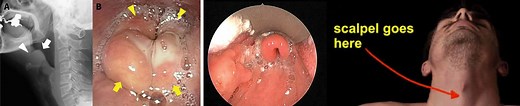

How Long Can Epiglottitis Last

What Is The Duration Of Epiglottitis? How Long Can Epiglottitis Last Useful Articles on the Topic Article Description Site Epiglottitis: Symptoms,...

Epiglottitis